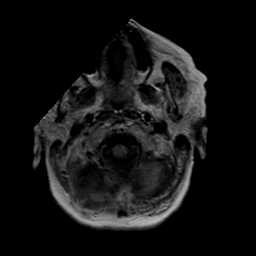

Stroke: proton density-weighted MR #2 -- Slice #0

[Home][Help][Clinical] Slice 0